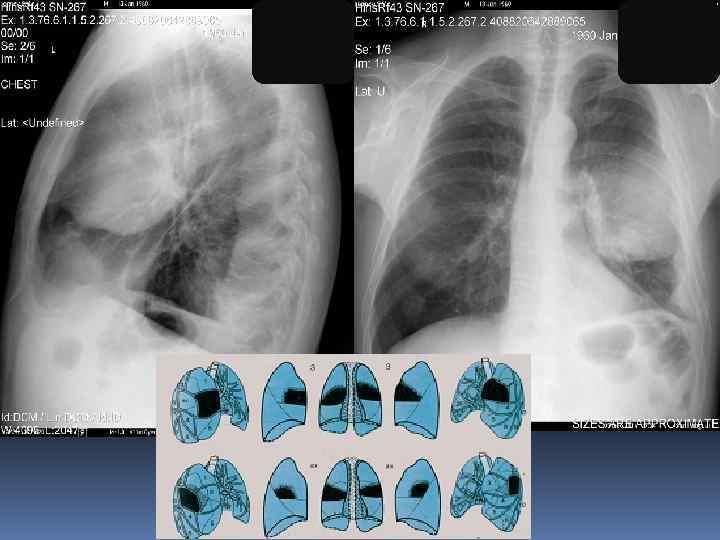

Изменение гемодинамики малого круга – ЛВГ, ЛАГ, интерстициальный отек

Изменение гемодинамики малого круга – ЛВГ